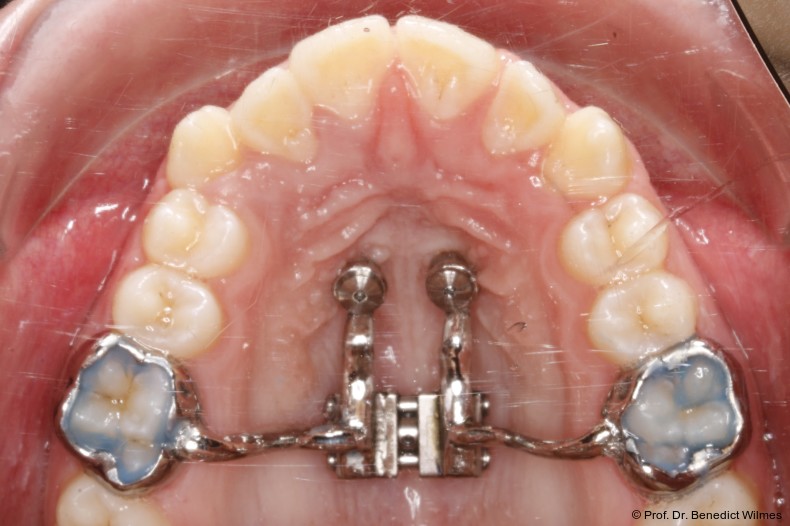

Klinisches Prozedere

Die initiale Behandlung erfolgte mit einer CAD/CAM Hybrid Hyrax zur Expansion des Oberkiefers, verankert an zwei paramedianen Miniimplantaten (Abb. 4, Benefit, 2,0 x 9,0 mm). Anstelle klassischer Molarenbänder wurden Shells (geklebte Kappen) verwendet, wodurch die beiden Schritte Separieren und Anpassen von Molarenbändern entfallen. Die Miniimplantate und die Apparatur wurden dank eines Inser­tionsguides in nur einer Sitzung eingesetzt.

Die Shells wurden mit lichthärtendem Kom­posit befestigt. Nach Expansion des Oberkiefers (Abb. 5a–f) erfolgte eine Retentionsphase von neun Monaten, in der die Hybrid Hyrax in situ belassen wurde.

Nach dieser Rentionszeit wurde die Hybrid Hyrax entfernt und ein Scan zur Herstellung der Molarenintrusionsapparatur (digitale Mause­falle) durchgeführt. Die beiden Miniimplantatköpfe lassen sie dabei sehr gut scannen, so­genannte Scan-Bodies sind in der Regel nicht mehr notwendig. Die digitale Mousetrap-­Appa­ratur besteht aus zwei Teilen (Abb. 6):